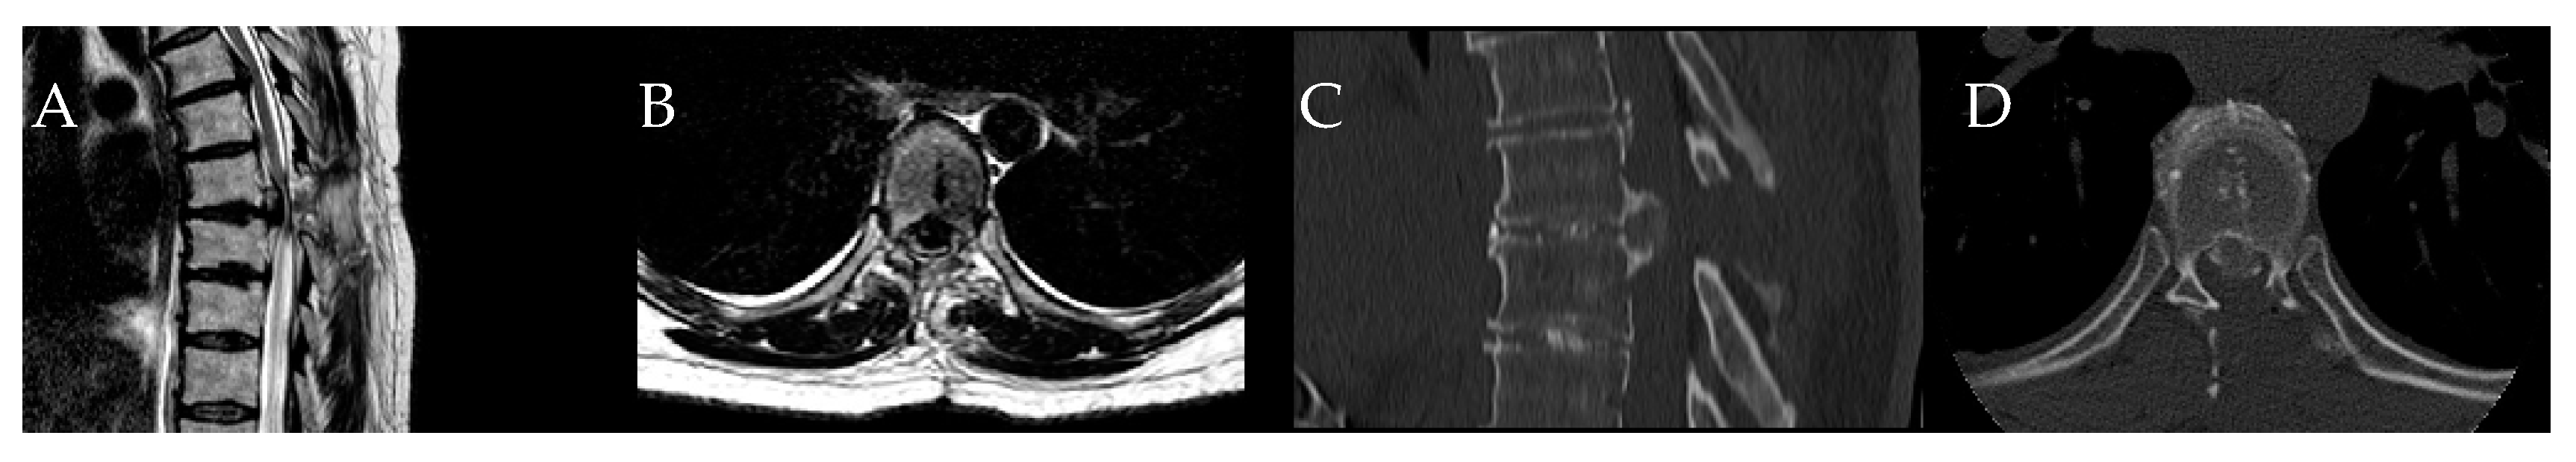

4. Patients